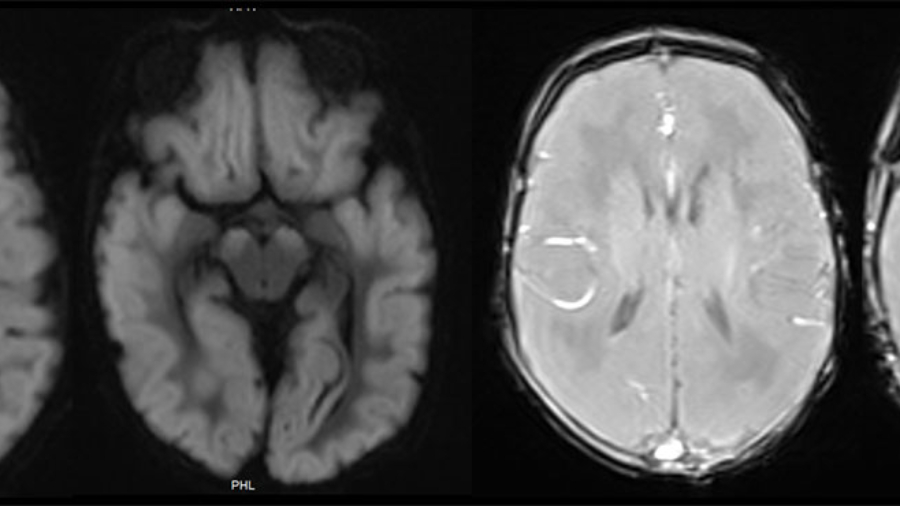

A term, appropriate-for-gestational-age neonate with normal APGAR scores and no history of perinatal hypoxia presented with seizures on day 2 of life.